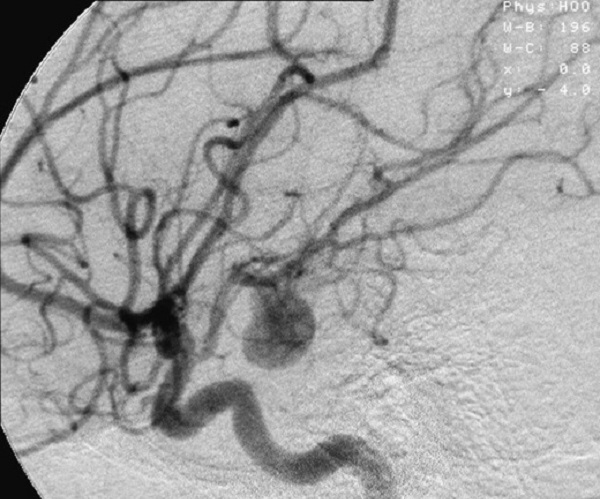

Halk arasında genelde baloncuk olarak bilinen “Anevrizma” hakkında bilgilendirmelerde bulunan Prof. Dr. Çırak, “Toplum içerisinde haberi olmadan beyninde anevrizma ile yaşayan çok fazla kişi var. Kanama olmazsa hiçbir belirti vermeden gidebildiği yere kadar gidiyor” dedi.

Özel Denizli Tekden Hastanesi Beyin ve Sinir Cerrahisi Uzmanı Prof. Dr. Bayram Çırak, halk arasında genelde baloncuk olarak bilinen anevrizma, hakkında önemli açıklamalarda bulundu. Damarlardaki genişleme ya da beyin damarlarından dışarıya üzüm tanesi gibi taşma sonucu oluşan balonlaşma durumuna anevrizma olarak tanımlandığını ifade eden Prof. Dr. Bayram Çırak, “Halk arasında genelde baloncuk olarak bilinen anevrizma, damarlardaki genişleme ya da beyin damarlarından dışarıya üzüm tanesi gibi balonlaşma sonucu oluşan genişleme durumuna denir. Anevrizmada damar duvarı inceldiği için en küçük bir tansiyon fırlamasında, kabızlık, hapşırık gibi kafa içinde basıncı değiştiren günlük olaylarda bile kanama ile karşımıza çıkabildiği için çok önemlidir. Sebep ne olursa olsun kanama yaptığı için tablo çok ağır seyrediyor. Hastalarımız ensede ya da başın bazı bölümlerinde bomba patlaşmış gibi şiddetli bir ağrı ile bize başvuruyorlar. Toplum içerisinde haberi olmadan beyninde anevrizma ile yaşayan çok fazla kişi var. Dünya literatüründe bu oranlarla ilgili çeşitli bilgiler mevcut. Hatta bilinenden daha yüksek bir rakam olduğunu biliyoruz. Çünkü bu oranlar çeşitli sebeplerden dolayı hastanelere başvurmuş ve tesadüfen yakalanmış ya da kanama ile belirti vermiş hastalarda yapılan incelemeler sonrasında verilen oranlar. Yani tüm toplumu tararsak bu oran çok daha yükseklere ulaşabilir. Anevrizmalar kanadığı vakit ancak bilinebiliyor. Kanama olmazsa hiçbir belirti vermeden gidebildiği yere kadar gidiyor. Bir gün kişi tansiyonun bir anda yükselmesine bağlı patlama yaşarsa ancak o zaman anlaşılma ihtimali de var” şeklinde konuştu.